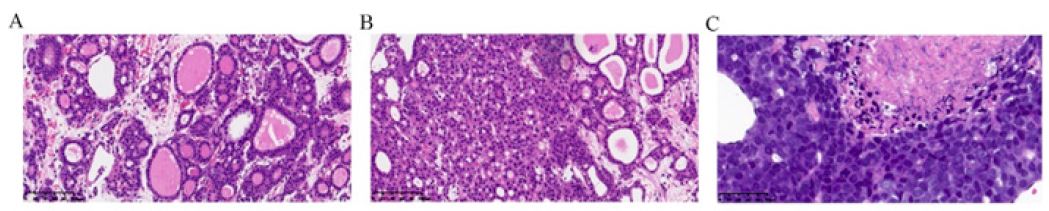

Three pieces of tumor tissues with 1.5 cm to 2 cm in lengths and 0.2 cm in wide were showed in pathological sections. Microscopically, The residual liver showed non-hepatitis and non-cirrhotic. The tumor has many follicles that vary in size. The tumor follicles, filled with eosinophilic colloid-like material within the lumens and lined with goiter-like vacuolation around the edge that highly resembles thyroid follicular tumor (Figure 2A). Macro and micro follicles grow in diffuse, nested or solid growth pattern. Inconsistent with reported literature, no clear nuclei, nuclear grooves or nuclear pseudo inclusions were present in the tissue and no papillary components were observed. Different from classical ICCA, dilated follicles in thyroid-like ICCA invade and destroy local hepatocytes but without desmoplasia surrounding. Lympho-vascular invasion was absent in the limited tumor tissue. In the solid areas, cells arranged cords or trabecular (Figure 2B). Some of them had obviously atypia, necrosis and mitotic figures (Figure 2C).

Figure 2: The morphological characteristics of Thyroid-like intrahepatic cholangiocarcinoma (HE stain). Nests of tumor cells arranged in cystically dilated glands with thin fiber spacing but without desmoplasia. Those glands contain colloid-like and brightly eosinophilic secretions reminiscent of thyroid follicles (A, x 200). Broad trabaculae of tumor cells were showed in the solid areas (B, x 200). High-grade tumor cells showed obvious atypia, including hyperchromatic and enlarged nuclei, scant cytoplasm, increased mitotic figures and extensive necrosis (C, x 400).